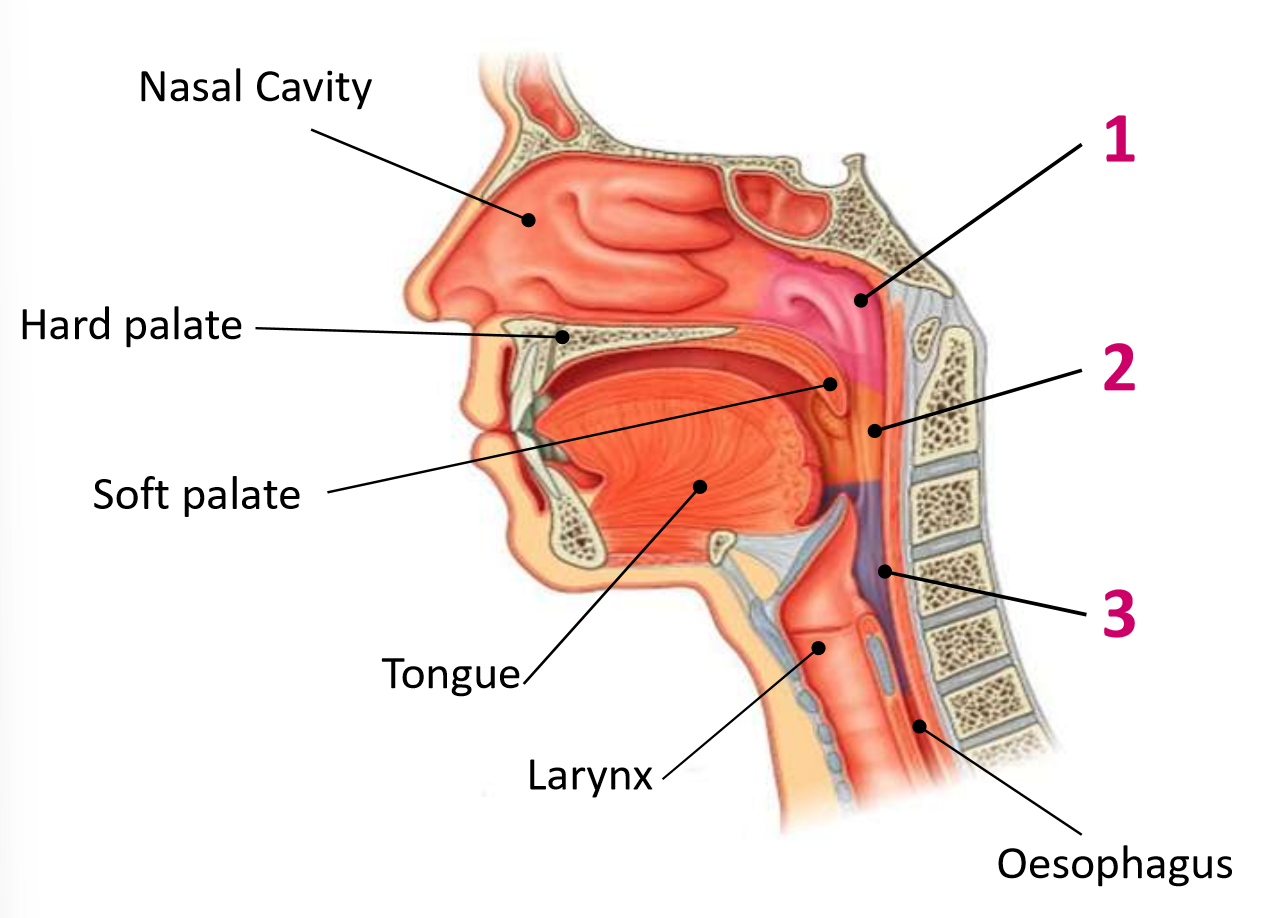

Which area of the head and neck do 1, 2, and 3 make?

pharynx

What region is 1?

nasopharynx

What region is 2?

oropharynx

What region is 3?

laryngopharynx